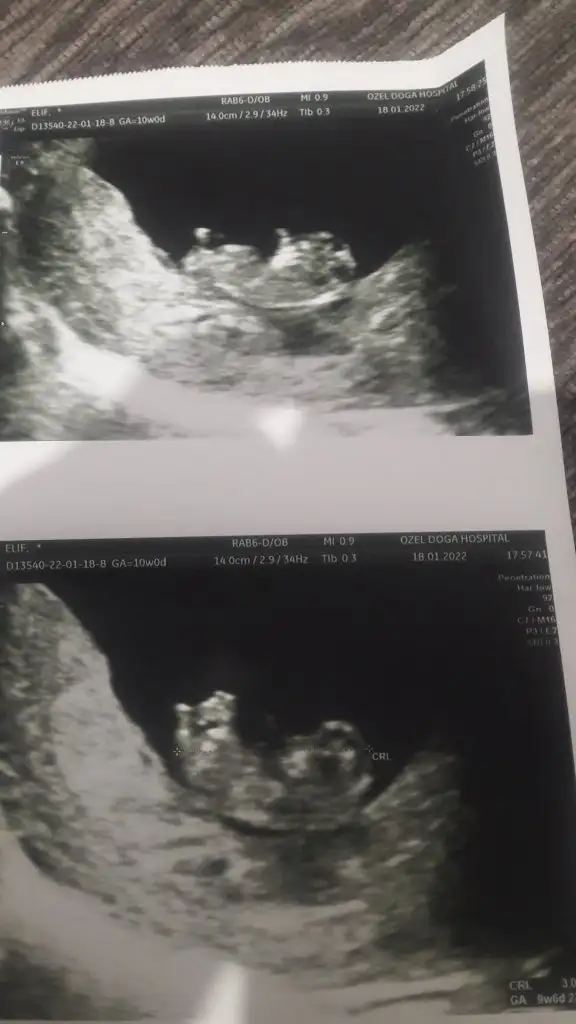

Tahmin alabilirmiyim tekrar 12 haftalik olduk

Eklentiler

• IMG-20220111-WA0003.webp

IMG-20220111-WA0003.webp

20,1 KB · Görüntüleme: 54